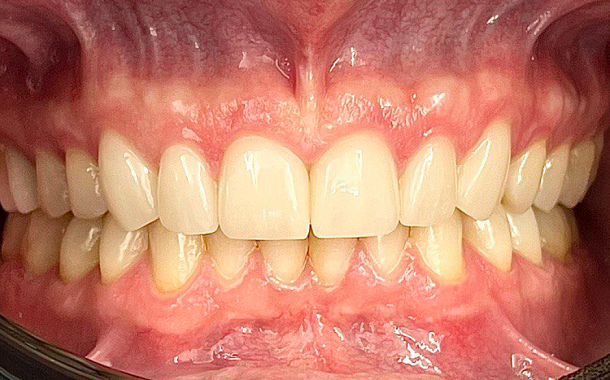

Полный прайс-листКейсы: до и после